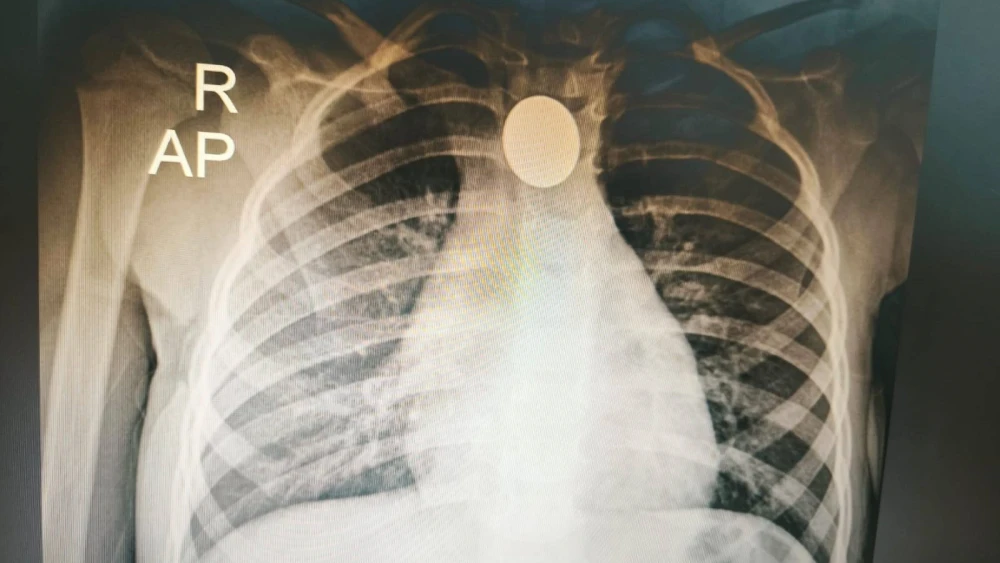

Una placa de tórax confirmó que se había tragado una moneda que le dificultaba la respiración. Los médicos del hospital no pudieron realizar una endoscopía y los médicos decidieron trasladarla al Instituto Nacional de Enfermedades Respiratorias y del Ambiente (Ineram).

La moneda de G. 100 que fue sacada del interior de la niña gracias a un hábil procedimiento.Foto: Gentileza-Dr. Carlos Morínigo.